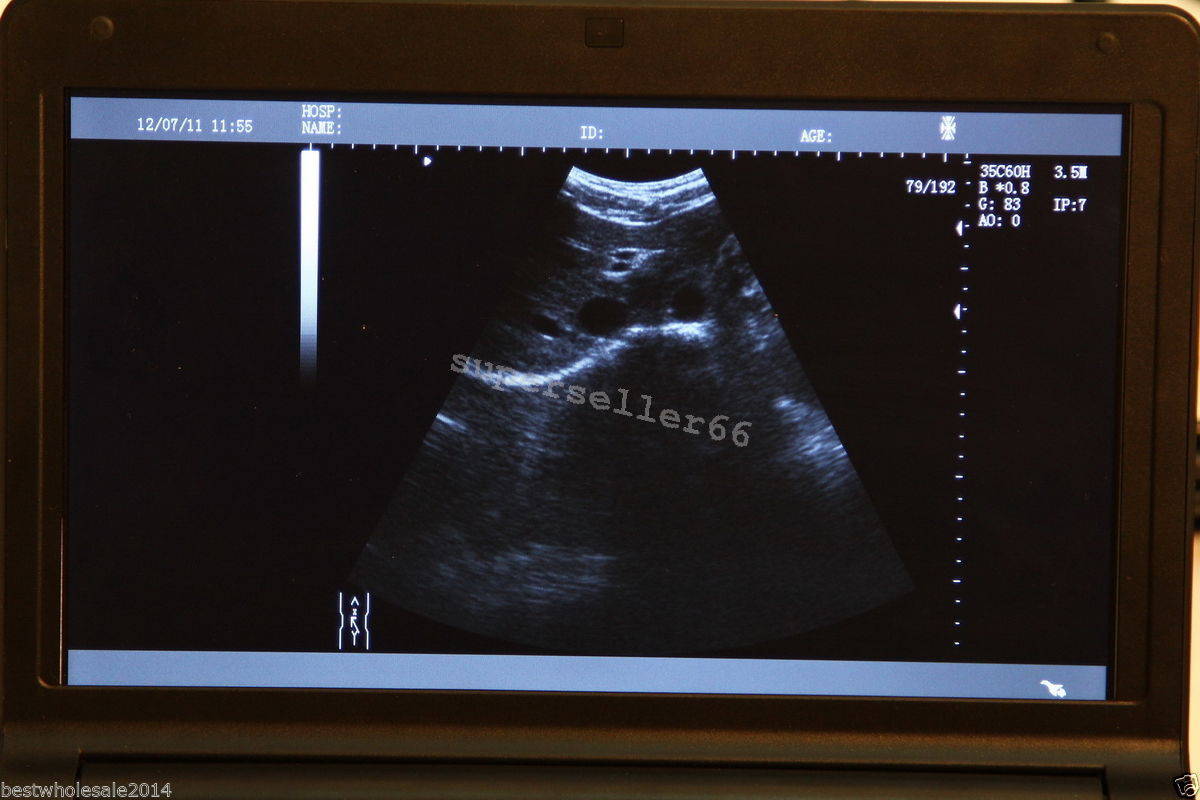

High-Resolution Display for Clear Imaging

The Ultrasound Scanner features a 10.1'' LCD screen that provides high-resolution images, ensuring that healthcare professionals can make accurate diagnoses. However, the clarity of ultrasound imaging is vital, because it directly impacts patient care. The intuitive interface makes it easy for users to navigate through various options, so they can focus on delivering quality healthcare.

Image mode: B, B+B, 4B, B+M, M

monitor: 10.1â high-resolution TFT LCD